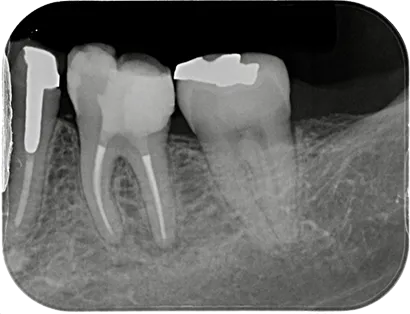

当院の症例を掲載しています。

当院での治療をご検討されている方は是非ご覧ください。

虫歯など様々な理由で歯の内部に細菌感染が広がることがあります。歯内療法(根管治療)とは、文字通り歯の内部の治療で、感染が広がった根管(神経が通る管)に対して適切な治療を行うことにより歯の機能を回復させることができます。